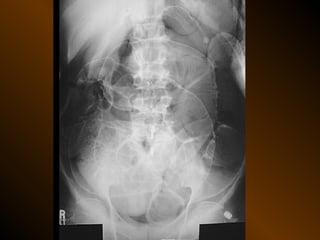

TỤ DỊCH TRONG PHÚC MẠC

• X QUANG QUY ƯỚC

– Trong tiểu khung

– Dọc hai bên hông

– Giữa bụng